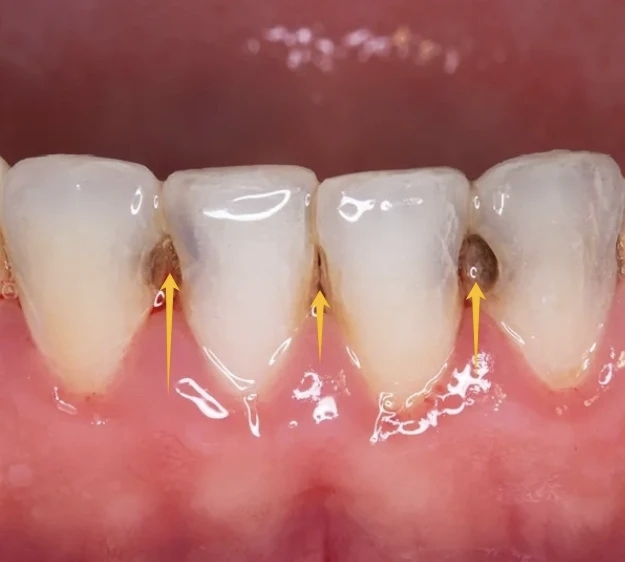

您是否曾发现,即使孩子认真刷牙,牙缝处还是容易蛀?这是因为牙菌斑最喜欢藏匿的地方,正是牙齿与牙齿之间紧密相接的邻面。这个区域是牙刷毛完全无法触及的“清洁盲区”。

可以做一个生动的比喻:只刷牙不用牙线,就相当于只洗了脸的一半,而永远没洗另一半挨着脸的脸。 食物残渣和菌斑长期堆积在牙缝中,不仅会导致邻面蛀牙(一种非常隐蔽且常见的蛀牙类型),还会引起牙龈红肿、出血,甚至口腔异味。

儿童牙缝同样需要清洁! 只要有两颗牙齿并排挨在一起,就是使用牙线的指征。这通常发生在后牙萌出之后,可能早在2-3岁就开始了。